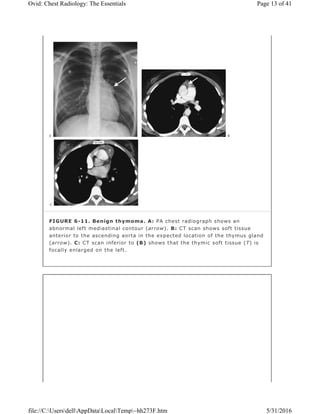

FIGURE 6-11. Benign thymoma. A: PA chest radiograph shows an

abnormal left mediastinal contour (arrow). B: CT scan shows soft tissue

anterior to the ascending aorta in the expected location of the thymus gland

(arrow). C: CT scan inferior to (B) shows that the thymic soft tissue (T) is

focally enlarged on the left.